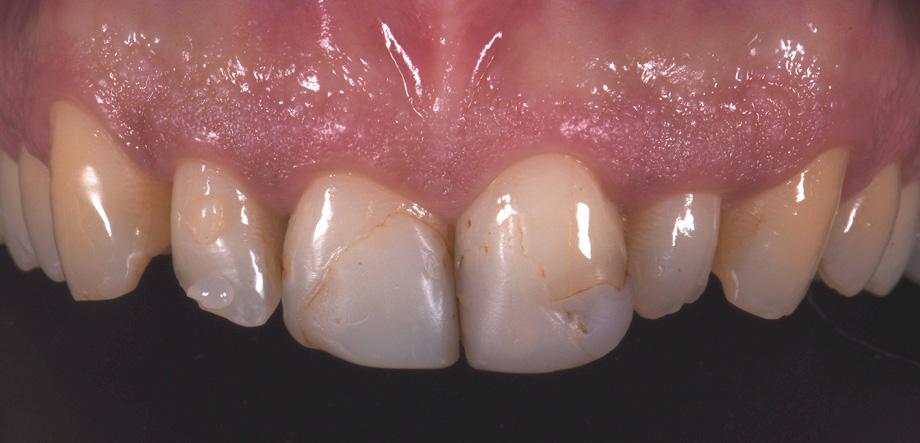

Figure 1 - Pre-Operative presentation, exhibiting a failed direct composite restoration on the upper left central incisor (Tooth 21).

The patient, a young male, was unhappy with the appearance of his maxillary anterior teeth. Several years ago, his central incisors had been restored with composite. These existing restorations had defective and heavily discoloured margins, while their shade did not match the adjacent natural tooth structure. The maxillary lateral incisors were peg-shaped (microdontia). Economic considerations and the desire to save as much natural tooth structure as possible made the team decide to restore all four maxillary incisors with composite. CLEARFIL MAJESTY™ ES-2 Premium became the material of choice as it eliminates the need for complicated shade combination formulas and supports predictable outcomes.

Restoring The Central Incisors

We decided to restore the central incisors first and then focus on the lateral incisors. The tooth shade was determined using the VITA™ classical A1-D4 shade guide, while composite buttons were applied to the teeth to verify the determined shade combination. In order to simplify the restoration procedure, a palatal silicon index was produced before removing the existing restorations.

Fig. 2 Intraoral image of the initial situation with defective composite restorations and microdonts. Two composite buttons on the right lateral incisor are used to verify the determined shade combination.

Fig. 3 Central incisors after removal of the old restorations and the beveling of the enamel.

During minimally invasive tooth preparation, bevels were created at the margins to provide for a smooth optical transition from the natural tooth structure to the composite.

An adhesive (CLEARFIL™ Universal Bond Quick) was applied after selective etching of the enamel to achieve a strong bond. With the aid of the silicon index, it was easy to create the palatal shells of the restorations with CLEARFIL MAJESTY™ ES-2 Premium in the shade A3E (enamel), which matches the determined tooth shade A3. The dentin core was built up with the same composite in the recommended shade A3D (dentin), mamelons were modelled and some CLEARFIL MAJESTY™ ES-2 Premium in the shade WD added for the incisal halo, while some individual effects (like enamel cracks) were imitated with brown stain. The build-up was finalized in the interproximal and labial areas with composite in the shade A3E. Between the central incisors, a wedge was used to retract the papilla and facilitate the designing of the interproximal contact area. The finished and pre-polished restorations already had a natural appearance.